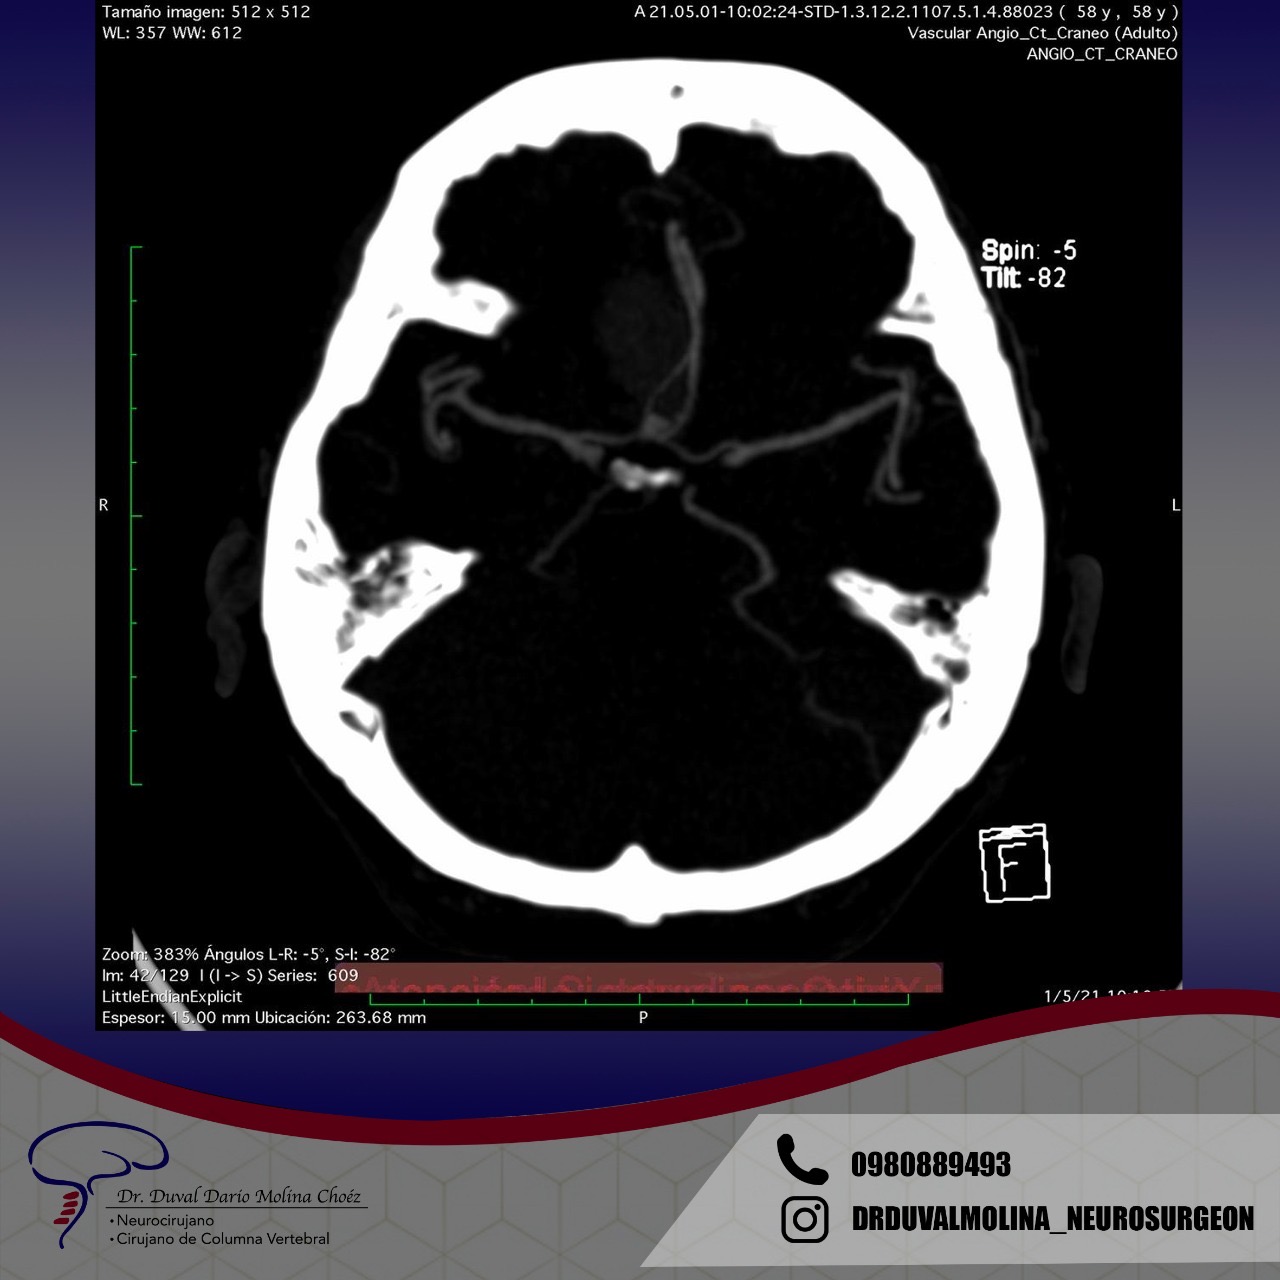

Los aneurismas son un abultamiento de una pared arterial que representa un punto débil. Se encuentran en alrededor del 2-3% de la población y suelen permanecer en silencio hasta que se rompen. Un aneurisma roto generalmente se presenta con el peor dolor de cabeza que haya existido y un inicio rápido de problemas neurológicos. El patrón característico de la hemorragia se denomina «hemorragia subaracnoidea».

También puede causar la muerte instantánea o provocar una discapacidad permanente. En algunos casos, hay un fuerte historial familiar o una condición genética. La afección hereditaria más común es la enfermedad renal poliquística del adulto. Los factores de riesgo para la ruptura del aneurisma incluyen el tabaquismo, la hipertensión mal controlada y el esfuerzo excesivo. Si no se trata, existe un riesgo anual acumulativo de ruptura y se recomienda una vigilancia periódica.

El patrón de hemorragia típico que se observa después de la ruptura de un aneurisma. La forma y la ubicación del aneurisma pueden predecir su comportamiento y también determinar qué opción de tratamiento es probable que sea la mejor. Alternativamente, si el aneurisma representa un bajo riesgo de ruptura o un alto riesgo quirúrgico, podemos optar por seguirlo con imágenes en serie. La intervención está diseñada para detener el flujo de sangre hacia el aneurisma, eliminando así el riesgo de hemorragia. Se puede realizar de forma endovascular rellenando el aneurisma desde dentro («coiling» endovascular), o mediante técnicas microquirúrgicas abiertas («clipaje»).